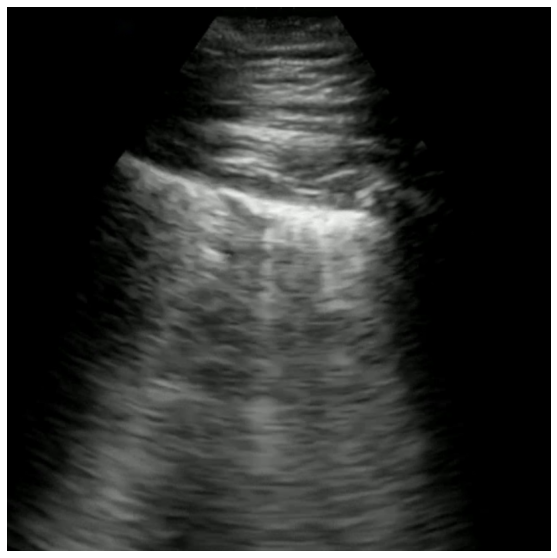

For example, POCUS images captured using a convex probe have a greater field-of-view with a cone shaped viewing window. This window differs in its viewing angle from device to device, and can also have a variety of forms as shown in Figure 1. In contrast, POCUS images captured using a linear probe has a more restricted field-of-view, but have a linear viewing window with visual content appearing distorted compared to that of images captured using a convex probe.